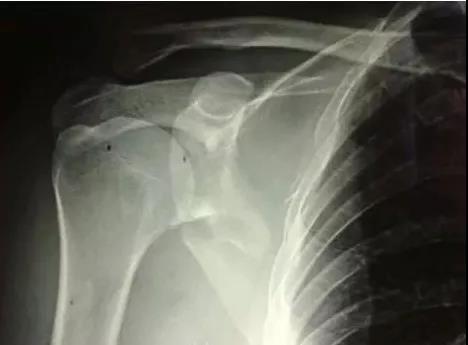

(2)肩胛带骨折

1)锁骨骨折

当骨折块伤及锁骨下动、静脉和臂丛神经时,一致认为是严重的并发症,应立即手术。

2)肩胛骨骨折

在2周之后手术,困难程度翻番。